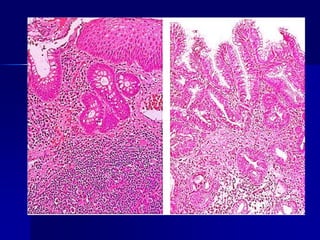

Un hombre de 33 años con una historia de diarrea crónica de 5 años ha perdido recientemente 6 kg y se

fatiga crónicamente. Una muestra de biopsia de su yeyuno (arriba ) se compara con una muestra de biopsia

yeyunal normal (abajo). Después de cambio en la dieta, mejora.

1. ¿Cuál es su diagnóstico?

2. ¿Qué pruebas serológicas pueden ayudar en el diagnóstico?

3. ¿Cuál fue el cambio en la dieta?

4. ¿Qué condición de la piel puede acompañar a esta enfermedad?